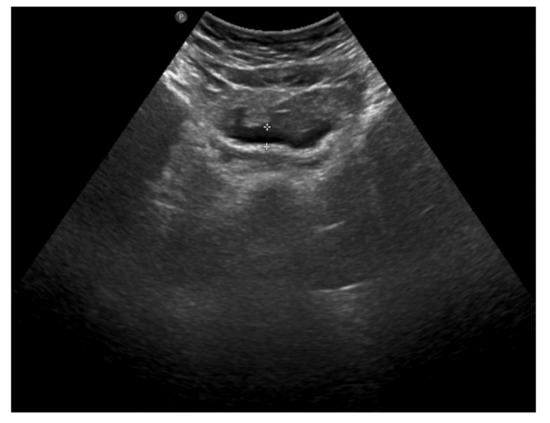

An abdominal ultrasound was then performed (Figure 2) and showed mesenteric adipose tissue along the right flank, with increased echogenicity. There was fluid in the pouch of Douglas, with a layer thickness of up to 25 mm, along with a trace of free fluid, both interloop and perihepatic. The appendix was not visualized, which prompted a further diagnostic work-up.

Figure 2. The abdominal ultrasound on admission: mesenteric adipose tissue with increased echogenicity and free fluid.